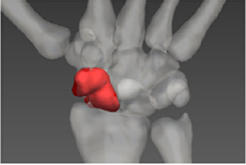

充分发挥专业优势,同积水潭医院深入开展红色“1+1”支部共建活动,通过建立手舟骨CT和金标准数据库,显著提高手术效率及准确率。该技术应用以来,受益人数上万人。

技术钻研,助力智慧医疗。MedAI实验室与301医院、中日友好医院、北京协和医院等多家三甲医院合作,将信息技术与医疗相结合,研发了一系列医学影像智能分析算法,为上千余例手术提供技术支持,促进了学科交叉发展和成果落地,以科技助力智慧医疗。